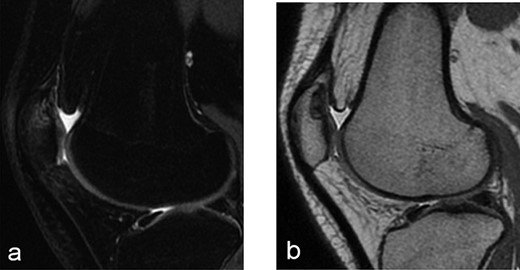

A 14-year-old female dancer presented with increasing right knee pain and functional disability without any trauma. Her pain was retropatellar pain that often radiated medially or laterally from the patella, exacerbated by climbing stairs, running and squatting. She was unable to perform any sports activities. Examination revealed peripatellar tenderness and crepitus, full range of motion and the knee was stable. Radiological examination included both MRI and computed tomography of the knee were performed at the beginning. MRI showed osteochondritis dissecans at the area at the superolateral facet of the patella in the deep subchondral area as shown in Fig. 1. This was appropriately treated conservatively with 6 months of reduced load and protected weight bearing without relief of symptoms. She quit sport activity for 2 years and then another MRI was performed Fig. 2. After 2 years we opted for adipose-derived mesenchymal stromal cells (AD-MSCs) intra-articular therapy according to the procedure described by Tremolada et al. [9]. The patient’s parents were given written information regarding the use of AD-MSCs therapy, including relative risks of this therapy and also relevant treatment alternatives that could otherwise be explored. Postoperative radiological evaluation was performed at 6 months and 12 months after AD-MSCs procedure as shown in Figs. 3 and 4. Postoperative clinical evaluation was performed using IDKC, Lysholm and Tegner scores (Table 1). After surgery, patients began a McConnell program of lateral retinacular stretching, patellar taping and vastus medialis obliquus muscle exercises. The patient was encouraged to swim and cycle to reduce impact loading. Using AD-MSC, she reported a complete relief of pain after 1 year from the procedure. Routine MRI follow-up 2 years later showed evidence of appreciable improvement in cartilage volume and osteochondral architecture at the site of injury. Early MRI T2 mapping at 6 months indicated that the area of cartilage regeneration exhibited high water content suggestive of immature cartilage or fibrocartilage morphology. Later T2 mapping at 18 months after the procedure, indicated progressive maturation of cartilage from deep to superficial layers with more hyaline like cartilage morphology. Limitations of the study are lack of arthroscopic intra-articular visualization and classification of the patella lesion.

Radiographs of the patient’s knee at 14 years old (a) Axial T2-weighted MRI sequences (b) sagital T2-weighted MRI sequences showed abnormality area at the superolateral facet of the patella in the deep subchondral area, this area of altered signal, hypointense in T1 and hyperintense in T2 with a shaded surrounding edema, was oval in morphology and had a craniocaudal extension of about 12 mm and transversal about 10 mm, the lesion interrupted the corresponding patellar articular cartilage which appears swollen in this position (c) axial computed tomography scan showed loss bone at that same point of patella in the right knee.